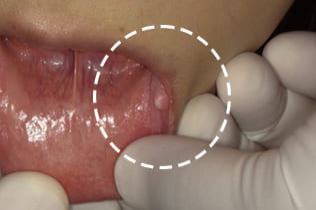

「40歳代 男性」口唇の弾性軟の腫瘍を主訴に来院されました。粘膜下に黄色色の腫瘤性病変を認め、弾性軟であったことより、口唇での発生はまれなものの、脂肪腫あるいは線維腫と診断して病理組織診断を確定させることも目的に患者さんと相談して摘出術を施行しました。

眼瞼翻展器を用いて口唇を把持します。これにより局所の止血が適切に行うことができ、また、腫瘍を水平な面で把持することができます。局所浸潤麻酔を行います。